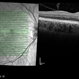

- paracentral acute middle maculopathy, OCTA

- OCT-A of a 30 yo female with PAMM OD.